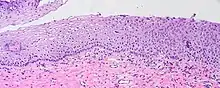

Visualization of koilocytes

Koilocytes can be visualized microscopically when tissue is collected, fixed, and stained. Though koilocytes can be found in lesions in a number of locations, cervical cytology samples, commonly known as Pap smears, frequently contain koilocytes.[5] In order to visualize koilocytes collected from the cervix, the tissue is stained with the Papanicolaou stain.[5] Another way koilocytes can be visualized is by fixation of tissue with formalin and staining with hematoxylin and eosin, commonly known as H&E.[5] These stains give the cytoplasm and nuclei of cells characteristic colors and allows for visualization of the nuclear enlargement and irregularity, hyperchromasia, and perinuclear halo that are typical of koilocytes.